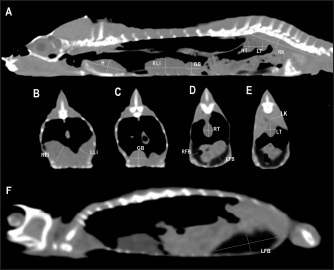

Heart, liver, including caudal vena cava (CVC), hepatic vessels, and gallbladder, esophagus, stomach, intestines, cloaca, gonads, fat bodies, kidneys, and when distended, urinary bladder were identified in the CT images with the aid of the anatomical sections (Fig. 4). The spleen, pancreas, and adrenal glands could not be identified. Measurement values of the liver, testes, fat bodies, and kidneys observed in CT in veiled and panther chameleons are seen in Table 1.

Fig. 4. Sagittal precontrast CT image displayed in soft tissue window (A) and transverse cross-sectional views of gross anatomical sections at the level of the liver (B), gallbladder (C), fat bodies (D), and kidneys (E) in a veiled chameleon (C. calyptratus). The right of the patient is on the left of the image. H, heart; RLu, right lung; LLu, left lung; Es, Esophagus; RLi, right liver lobe; LLi, left liver lobe; ST, stomach; GB, gallbladder; RK, right kidney; LK, left kidney; RT, right testicle; LT, left testicle; RFB, right fat body; LFB, left fat body; Co, colon.

Fig. 5. Sagittal precontrast CT image displayed in soft tissue window (A) and selected corresponding transverse images represented as green line section, displayed in soft tissue (B, D–G) and lung window (C) at the level of the lungs, liver (D), gastrointestinal tract (E), fat bodies (F), and kidneys/urinary bladder (G) in a panther chameleon (F. pardalis). The right of the patient is on the left of the image. RLu, right lung; LLu, left lung; Es, esophagus; RLi, right liver lobe; LLi, left liver lobe; St, stomach; I, intestine; GB, gallbladder; RK, right kidney; LK, left kidney; RT, right testicle; LT, left testicle; Co, colon; RFB, right fat body; LFB, left fat body; U, urinary bladder with intraluminal content (urate salts) in the lumen visualized as multiple irregular mineral attenuating structures.

Fig. 6. Sagittal right paramedian precontrast CT image displayed in soft tissue window (A) and selected corresponding transverse images represented as green line section, displayed in soft tissue window at the level of the gallbladder (B), fat bodies (C), and kidneys/urinary bladder (D) in a veiled chameleon (C. calyptratus). H, heart; RLu, right lung; LLu, left lung; Es, esophagus; RLi, right liver lobe; LLi, left liver lobe; GB, gallbladder; RK, right kidney; LK, left kidney; RT, right testicle; LT, left testicle; I, intestine; RFB, right fat body; LFB, left fat body; U, urinary bladder; LF, left femur; RF, right femur; PB, pelvic bone.